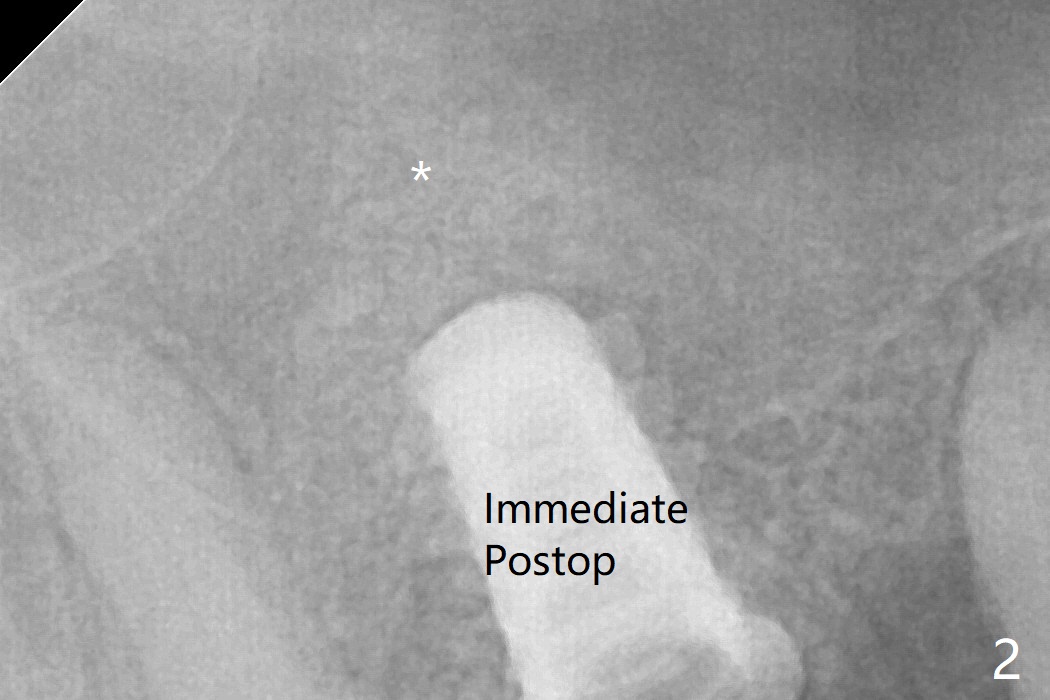

The bone graft in the sinus seems to collapse and condense 10 months postop (Fig.7 *).